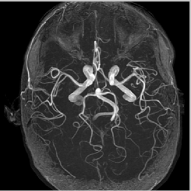

Finally, we show the recovery of four MR images from three fold radial under sampled data that is contaminated with zero mean complex Gaussian noise of standard deviation σ=10𝜎10\sigma=10. These experiments show that the NLS scheme can be used to obtain good quality reconstructions at moderate acceleration factors and noise levels.

Refer to caption

(a) Circle of Willis

(b) Spine

(c) Brain3

(d) Brain4

(e) NLS,SNR=24.01

(f) NLS,SNR=29.43

(g) NLS,SNR=25.65

(h) NLS,SNR=24.75

(i) Error

(j) Error

(k) Error

(l) Error

Figure 7: Comparison of different MR images using NLS algorithms in the presence of noise. We consider the recovery from a three fold undersampled radial sampling pattern, contaminated by zero mean complex Gaussian noise with standard deviation σ=10𝜎10\sigma=10. The top two rows show the original and reconstructed images, while the error images scale by a factor of five are shown in the bottom row. We observe that the NLS scheme preserves well the edges and the fine details at low acceleration with presence of noise.